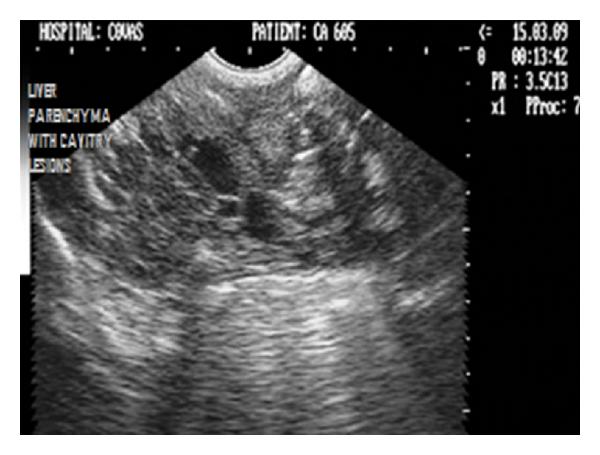

Hepatic disease is often treatable and has a predictable prognosis when a definitive diagnosis is made. The aim of clinicopathological evaluation of hepatobiliary affections is to identify and characterize hepatic damage and dysfunction, identify possible primary causes of secondary liver disease, differentiate causes of icterus, evaluate potential anaesthetic risks, assess prognosis and response to xenobiotics, and monitor response to therapy. This paper describes the different diagnostic methods and imaging techniques employed in diagnosis of hepatobiliary affections in dogs. Besides reviewing the significant clinical manifestations and imaging structural abnormalities in diagnostic approach to different hepatic affections, it also depicts radiographic, ultrasonographic, and wherever applicable, the laparoscopic characterization of different hepatic affections and target lesions encountered in clinical cases presented in the Teaching Veterinary Clinical Complex, COVAS, Palampur in the year 2007-2008.

肝病通常是可治疗的,一旦做出明确诊断,其预后是可预测的。肝胆疾病临床病理评估的目的是识别和描述肝损伤及功能障碍,确定继发性肝病可能的主要病因,鉴别黄疸的病因,评估潜在的麻醉风险,评估预后及对外源化学物质的反应,并监测治疗反应。本文描述了用于诊断犬肝胆疾病的不同诊断方法和成像技术。除了回顾不同肝病诊断方法中的重要临床表现和成像结构异常外,还描述了2007 - 2008年在帕兰普尔兽医临床综合教学中心(COVAS)出现的临床病例中不同肝病及目标病变的放射学、超声学特征,以及在适用情况下的腹腔镜特征。